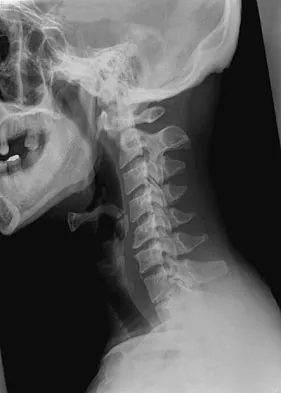

A 28-year-old professional dancer reports a 3-month history of progressive pain in the posterior aspect of the left ankle. Her symptoms are worse when she assumes the en pointe position. Examination reveals tenderness to palpation at the posterolateral aspect of the ankle posterior to the peroneal tendons which is made worse with passive plantar flexion. There is no nodularity, fluctuance, or tenderness of the Achilles tendon. The neurovascular examination is unremarkable. A lateral radiograph and MRI scan are shown in Figures 16a and 16b, respectively. Management should consist of

The imaging studies reveal findings typical of the os trigonum syndrome. This condition results from inflammation between the os trigonum and the adjacent talus. The symptoms of posterior ankle pain are exacerbated by plantar flexion, which stresses the fibrous union between these two bones. Definitive management of the high-level athlete involves excision of the os trigonum from a medial approach, although arthroscopic excision has also been described. The os trigonum is not an intra-articular structure; therefore, ankle arthroscopy is neither diagnostic nor therapeutic. Abramowitz Y, Wollstein R, Barzilay Y, et al: Outcome of resection of a symptomatic os trigonum. J Bone Joint Surg Am 2003;85:1051-1057. Mouhsine E, Crevoisier X, Leyvraz P, et al: Post-traumatic overload or acute syndrome of the os trigonum: A possible cause of posterior ankle impingement. Knee Surg Sports Traumatol Arthrosc 2004;12:250-253.